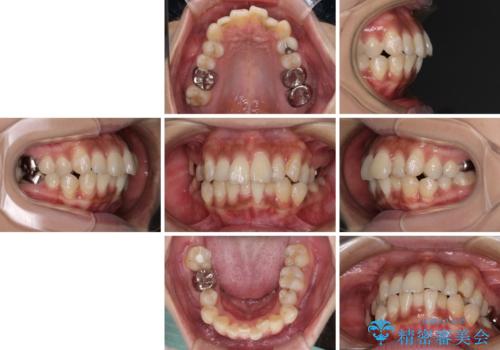

- 口元の閉じにくさを気にして来院された患者様です。

上下ともに歯列が前方に突出していたため、上下左右の第一小臼歯4本を抜去し、ワイヤー装置による矯正治療を行うこととしました。

舌の突出癖による影響もあったため、舌のトレーニングを並行して実施しました。

左下奥歯にむし歯が認められるため、矯正治療後にセラミックインレーにて修復治療を行うこととしました。

4本の歯を抜歯したことで、飛び出していた口元が引っ込み、横顔が大きく改善されました。